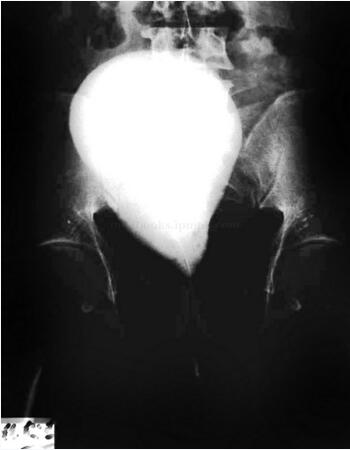

膀胱造影:膀胱位置上移、抬高,距耻骨联合约3cm,膀胱形似正置的“梨形”,盆部透明度明显增加(图46-5)。

图46-5 膀胱造影:膀胱位置上移、似正置的梨形